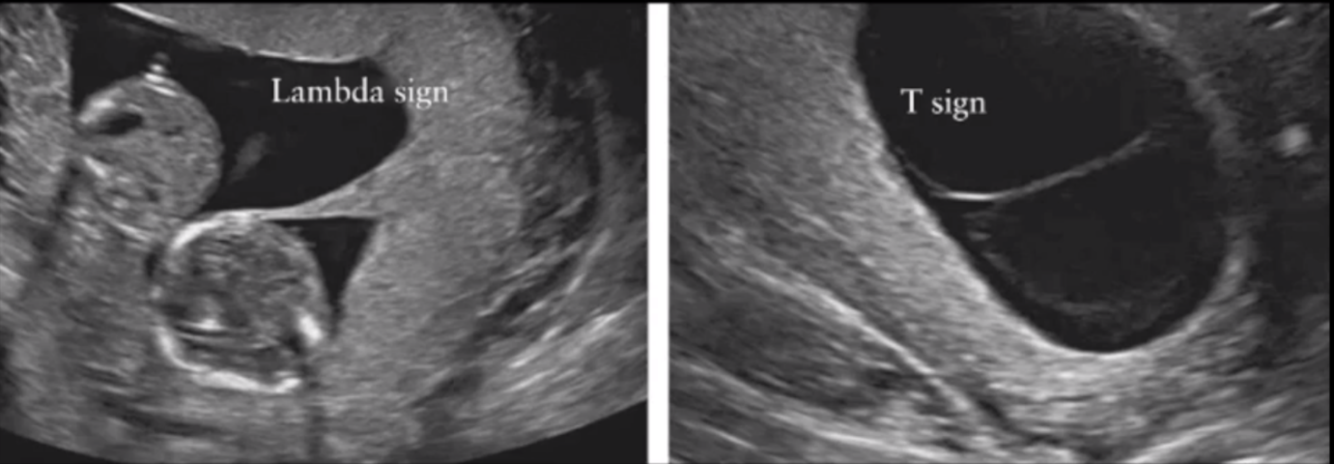

- Determination of zygosity and chorionicity is done by foetal USS

- Lambda sign shows 2 placentas – diagnosing dichorionic diamniotic twins

- T sign shows single placenta – diagnosing monochorionic diamniotic twins

Is a USS, what sign diagnosis dichorionic diamniotic twins and what sign diagnosis monochorionic diamniotic twins?

Lambda sign - dichorinic diamniotic twins (2 placentas)

T sign - monochorionic diamniotic twins (1 placenta)